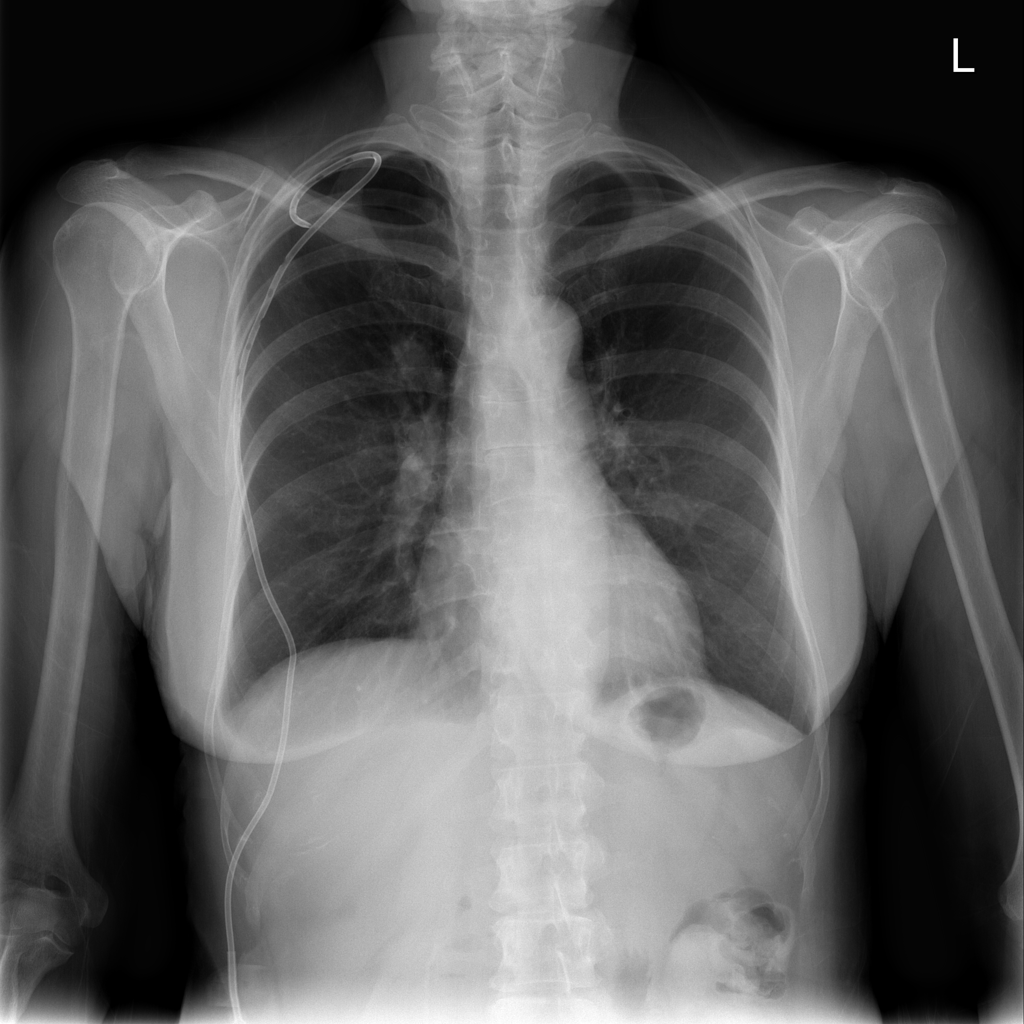

PAT-86C8 · IMG-000Effusion

PAT-86C8 · IMG-000

PA